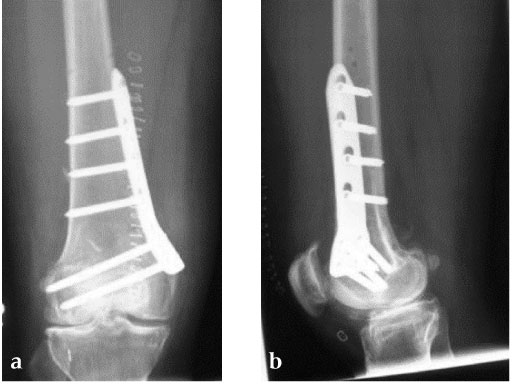

27-year-old male developed severe lateral joint line pain after lateral menicectomy.

Case provided by Philipp Lobenhoffer, Hannover, DE

An anteromedial skin incision is used. This skin incision can be reused and expanded during subsequent knee surgery. The vastus medialis muscle is dissected from the septum, the medial patellofemoral ligament (MPFL) and the distal insertion of the vastus medialis muscle are partially incised. Two blunt Hohmann retractors are placed around the distal femur. The oblique osteotomy starts in the medial supracondylar area and ends in the lateral condyle, approximately 10 mm inside the lateral cortex. For guiding the closing wedge osteotomy of the distal femur a specific saw guide will be available soon. Alternatively, it is possible to use K-wires inserted under image intensifier control to mark the bone cuts. The saw cuts are made with retractors protecting the soft tissue and vessels. The wedge is removed and the height and depth of the osteotomy can be measured. At this time it is possible to make modifications concerning the wedge size. Closing the wedge must be done gradually by gentle compression of the lower leg laterally, and stabilizing the knee joint medially near the area of osteotomy. This may take several minutes to enable plastic deformation of the lateral cortex to close the osteotomy gap. Leg alignment is checked radiologically after closing with a rigid alignment bar positioned between hip and ankle center. The bar representing the weight-bearing line should pass the preoperatively defined mechanical axis. The plate is inserted from distal under the vastus medialis muscle. The distal drill holes are oriented in a 20 angle inclination on the frontal plane to avoid a posterior perforation of locking head screws in the distal femur. The distal four bolts are placed. A lag screw is positioned in the dynamic hole directly above the osteotomy for compression of the osteotomy site. The screw should be tightened carefully using the image intensifier. The plate is now fixed to the shaft with bolts monocortically, and the lag screw is replaced by a bolt bicortically. The wound is closed in layers after insertion of a drain. The patient is mobilized on the first day after surgery. Partial weight bearing is recommended for 6 weeks, active movement of the knee is enhanced. Biomechanical testing confirmed superior stability of medial closing wedge techniques as compared to lateral open wedge techniques and favourable axial and torsional loading characteristics of the TomoFix medial distal femur (MDF) plate. The plate is now available, as well as a booklet on the operative technique.